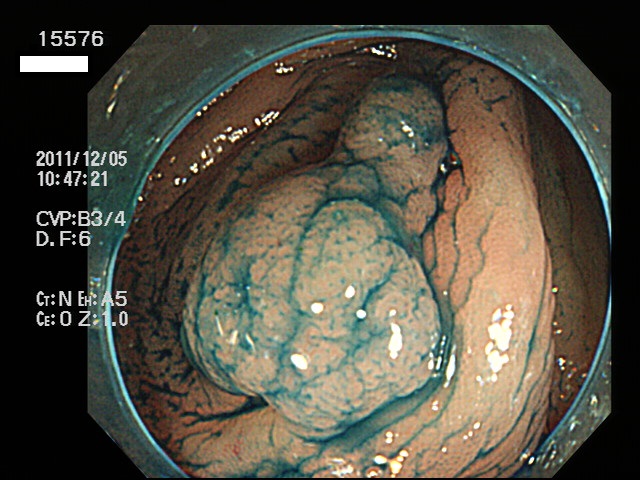

虫垂開口部の過形成ポリープ(SSAP)の例

一般に虫垂過形成ポリープが見られる方は「大腸の他の部位にもポリープ(特にSSAP)が見つかる可能性が非常に高い」のです。つまり「危険な腸である」という警告灯になるのです。虫垂は大腸の一番奥ですから「観察のスタート地点」です。ここで警告灯が出ることは非常に有益な訳です。